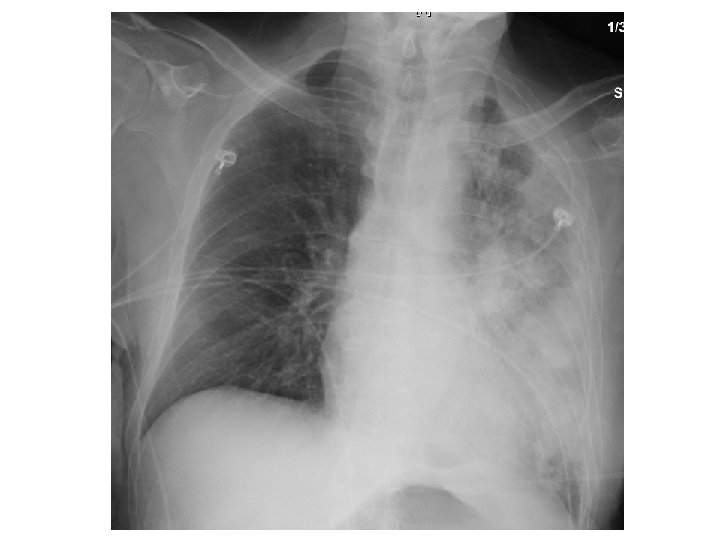

ER work-up • Abdominal XR = No obstruction/ air fluid level Atelectasis with central bronchial obstruction

Chest radiography • Active disease: upper lobe infiltration/ cavity/ effusion • Healed: nodules, fibrotic scars, calcified granulomas or basal pleural effusion • Normal in latent TB • HIV: infiltrate in any lung zone, mediastinal or hilar LAD, normal